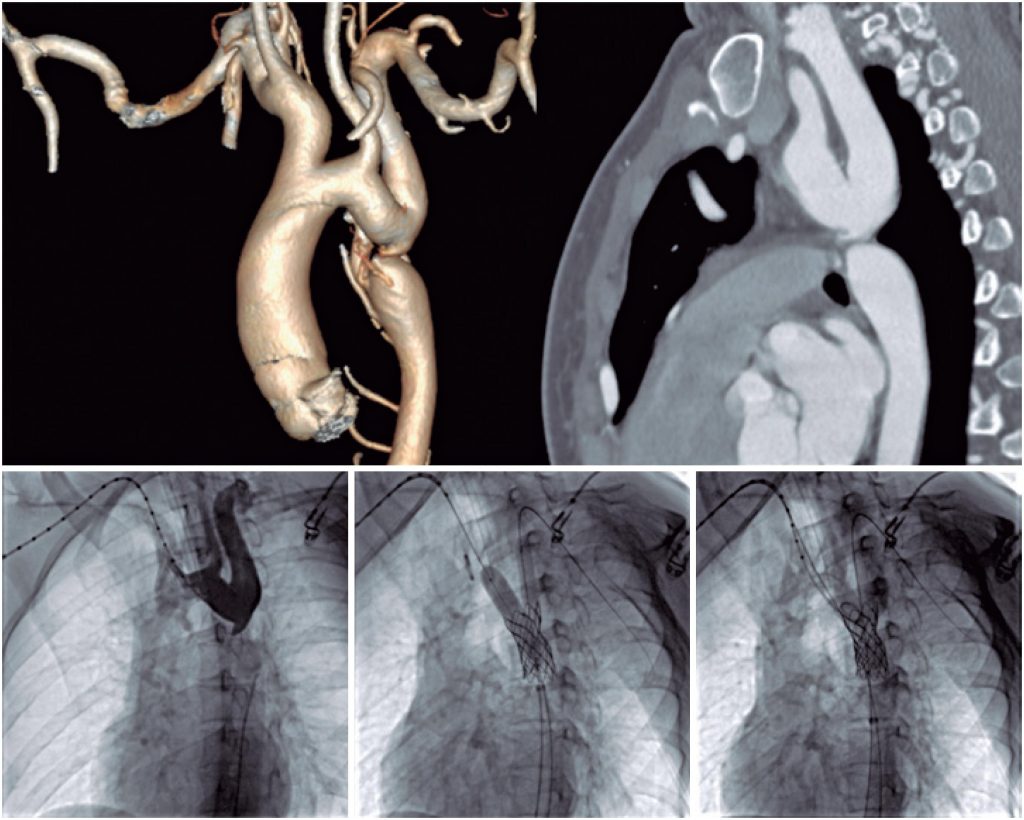

Transcatheter treatment of coarctation of the aorta with aortic lumen atresia and kissing balloon between the aorta and the left subclavian artery

Percutaneous treatment of CoA associated with aortic lumen atresia (ALA) is a technical challenge that requires specific materials, and is associated with an increased risk of complications. Farjat Pasos et al. described a technique for traversing the CoA with the assistance of an electrocautery, an accessible option when it is not possible to cross the lesion with 0.014” guides dedicated to the treatment of chronic occlusions using the traditional technique. In these cases, the implantation of covered stents is indicated. The narrowing of the aorta is generally distant from the origin of the left subclavian artery (LSCA), allowing the stent implantation to be performed without major difficulties. When the stenosis is close to the LSCA, the final kissing balloon (FKB) technique or a double guide for stent implantation can be used, ensuring patency of the branch.